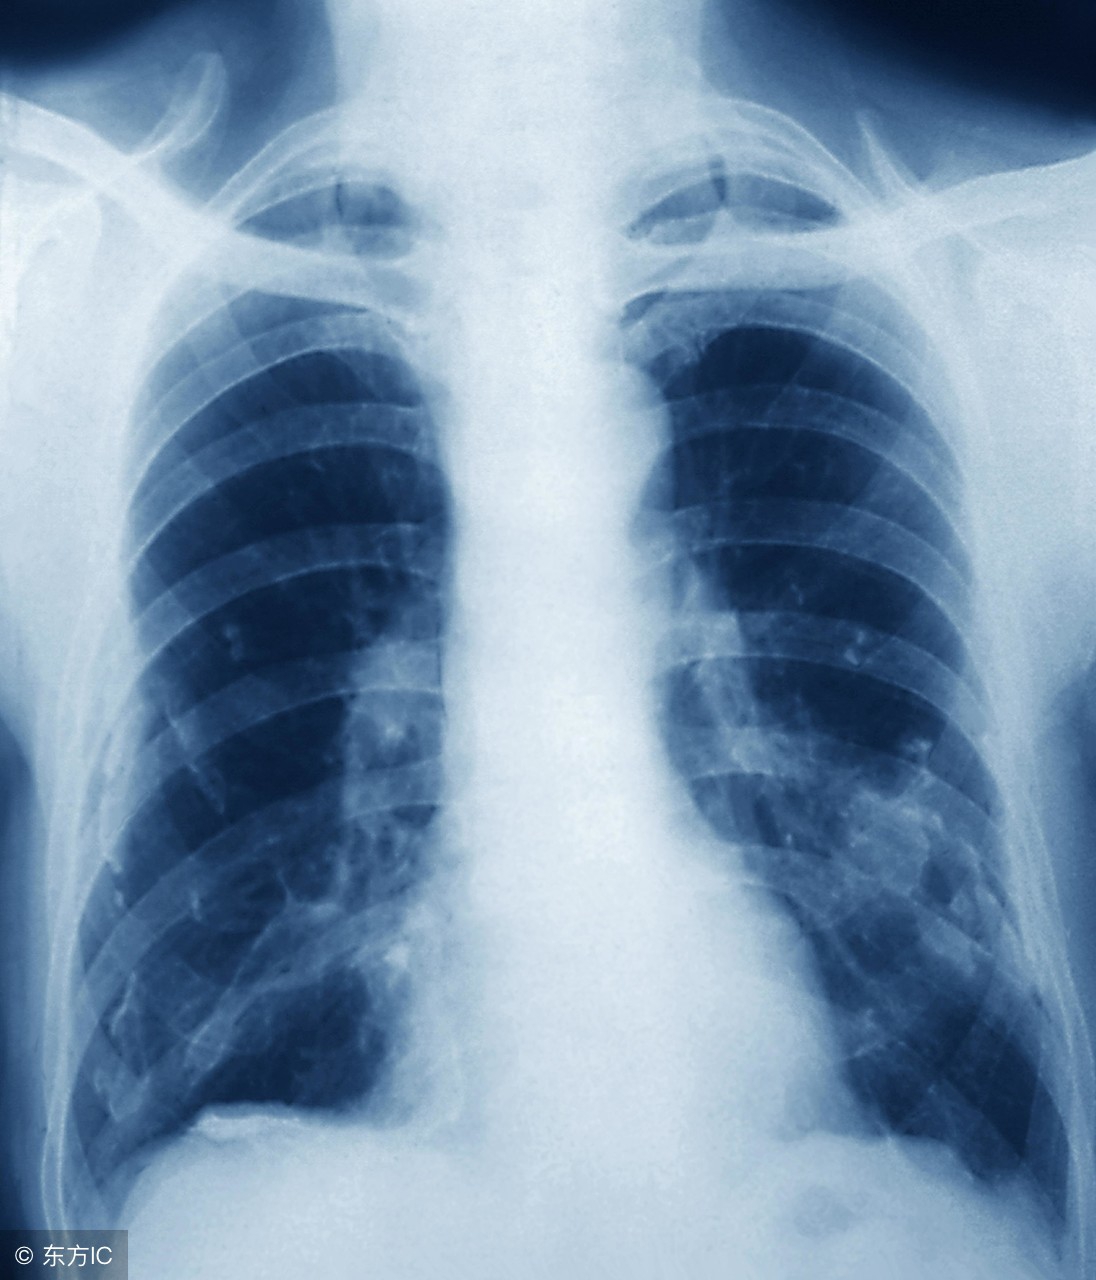

患有肺结核的症状是什么?患有肺结核会出现全身症状和呼吸系统症状。下面给大家详细描述一下肺结核的症状表现。

②咯血:相当多见,当肺部的任何病变损伤了血管时,便可出现咯血,咯血量的多少因血管损伤部位、大小不同而不同,痰中带血可因炎性病灶的毛细血管损伤所致,整口血痰是由于小的动静脉损伤,大咯血是损伤了大血管特别是肺动脉所致。对咯血病人,除应用止血剂外还应进行检查,如X线胸透或拍片,痰液检查,以明确咯血原因。